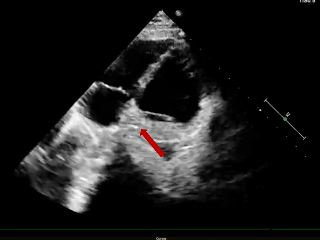

成型锁定

四腔心切面

主动脉短轴切面

封堵器呈“Y”字形牢牢抱住主动脉,夹持缺损